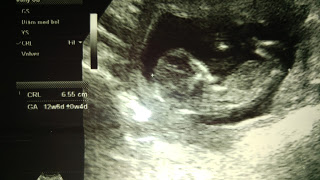

Vamos 28 semanas caminando juntos. Nos falta cada vez menos, y aunque me muero por verte la carita, olerte y darte un millon de besos por minutos, quiero disfrutar hasta la ultima patadita que des en mi panza.

No estabas en nuestros planes, llegaste sin avisar, sin que te llamemos, sin que te imaginemos. Pero dicen siempre que lo mejor llega así sin anunciarse, llega de repente y te deja una huella única en el corazón. Así llegaste mi pedacito.

"Hoy, 14 de enero de 2016, hace muy poquitas horas, me enteré que estas creciendo junto conmigo. No te puedo...